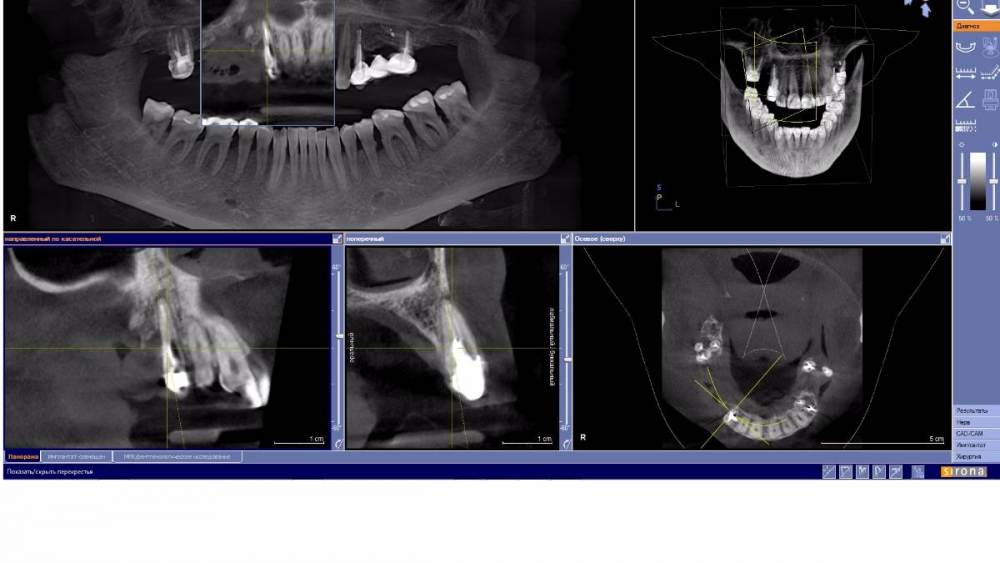

YnA Опубликовано 29 июня, 2021 Автор Поделиться Опубликовано 29 июня, 2021 wladdX, спасибо, что не прошли мимо! А конкретно что нужно удалить? Мне говорят 13,17,24,26. Ставить 7 имплантов. А на 17 и 26 есть воспаление? Можно ли делать синус лифтинг вместе с имплантами? Ссылка на комментарий

wladdX Опубликовано 29 июня, 2021 Поделиться Опубликовано 29 июня, 2021 Именно 13,17,24,26. Да, в области корней зубов 17 и 26 есть хронический воспалительный процесс. Да, во многих случаях возможно проведение имплантации при синус-лифтинге. В любом случае, принимать решение будет оперирующий Вас хирург. 1 Ссылка на комментарий